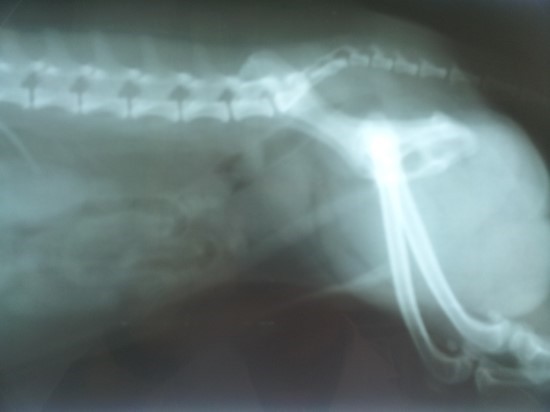

전립선암이 발생한 것을 모르고 전이로 인한 증상을 통하여 암을 발견하는 그럴 경우가 적지 않는다. 일부 환자는 조기에 원격 전이가 나타나기도 해요. 이러한 그럴 때에는 전립선 주변 부위를 광범위하게 침범하기도 합니다.. 골반 림프절이나 골반뼈, 척추뼈 등이 잘 전이되는 곳이에요.

3. 뼈 고통

뼈 고통은 엉덩이나 허리와 같이 전립선에 가깝게 위치해 있는 곳의 뼈에 통증을 호소하게 됩니다. 전립선암은 주로 척추 뼈, 어깨뼈, 골반 뼈, 늑골 등에 많이 전이가 발생하고 골절이 발생할 가능성이 있다. 신경통과 위에서 해당하는 뼈 고통으로 동일한 증상이 나타내기도 하므로 디스크 환자가 아니어도 허리에 고통이 생길 수 있으며, 이로 인하여 일상생활에 불편함을 느끼게 됩니다.